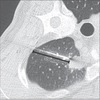

造影CT前の絶食は必要か

多くの画像診断センターは造影CT前に4〜6時間の絶食を患者に求めている。以前の研究では、長期間の絶食は有害である可能性が示されている。さらに、造影剤のメーカーは検査前に特別な準備は必要ないと主張している。本研究の目的は、がんセンターでの造影CT撮影前の絶食の効果を評価すること。

3206人を前向きに評価し、無作為に2つのグループに割り当てた。グループ1の1619人の患者は検査前に少なくとも4時間絶食したが、グループ2の1587人の患者は軽い食事をした。造影剤投与前後に観察された有害症状を群間で比較した。

造影剤投与後に発生した有害事象は、グループ1の患者45人(1.5%)およびグループ2の患者30人(0.9%)によって報告された。最も一般的な症状は悪心(n = 32)、脱力感(n = 12) 、および嘔吐(n = 5)。症状の頻度は、グループ間で統計的に有意な差はなかった(p> 0.05)。

がん患者を対象とした今回の集団では、造影CT前の絶食の有無に関係なく、ごくわずかな有害症状が報告された。これらの結果は、造影CTのための準備が単純化され、患者が経験する不快感および不便さを減少させることができるという考えを支持する。